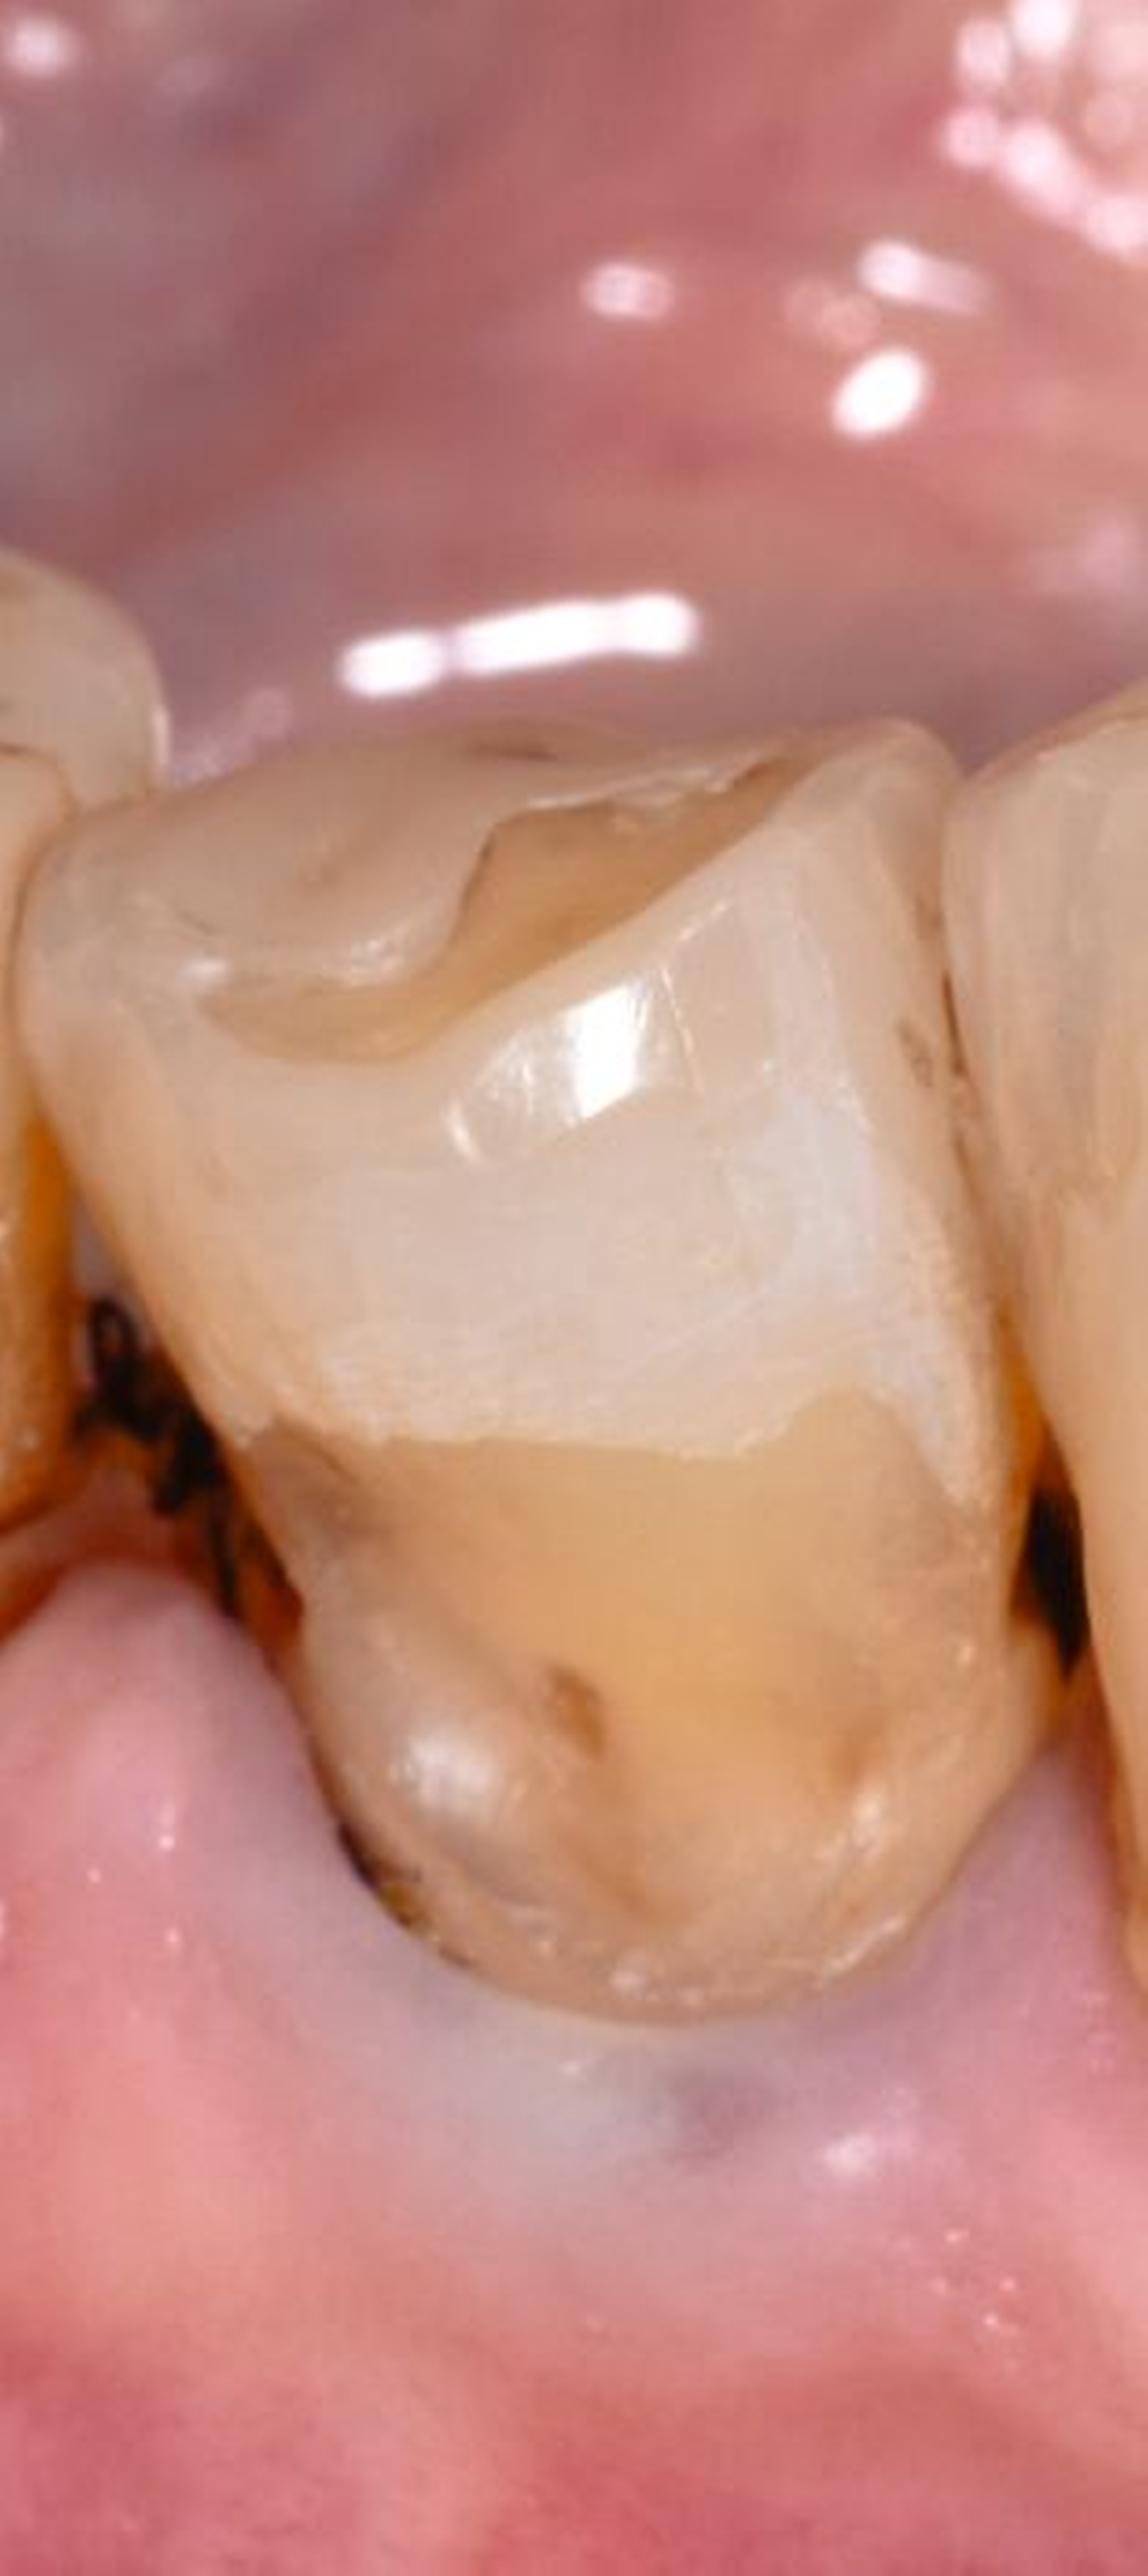

Die anschließende Ausarbeitung und Politur von Kompositrestaurationen ist erforderlich, um die Form der Restauration anatomisch korrekt zu gestalten, Überhänge, die einen Reiz für die umgebenden Weichgewebe darstellen können, zu entfernen und die Oberfläche zu glätten und somit zu vergüten. Polierte Kompositoberflächen sind widerstandsfähiger gegen Alterungs- und Abnutzungsvorgänge in der Mundhöhle. Raue Kompositoberflächen fördern die Plaqueakkumulation (Abbildung 3) und somit die Verfärbungstendenz des Materials. Die Glanzretention ist jedoch limitiert und je nach Ausgangsmaterial und Polierprozess unterschiedlich lang anhaltend.